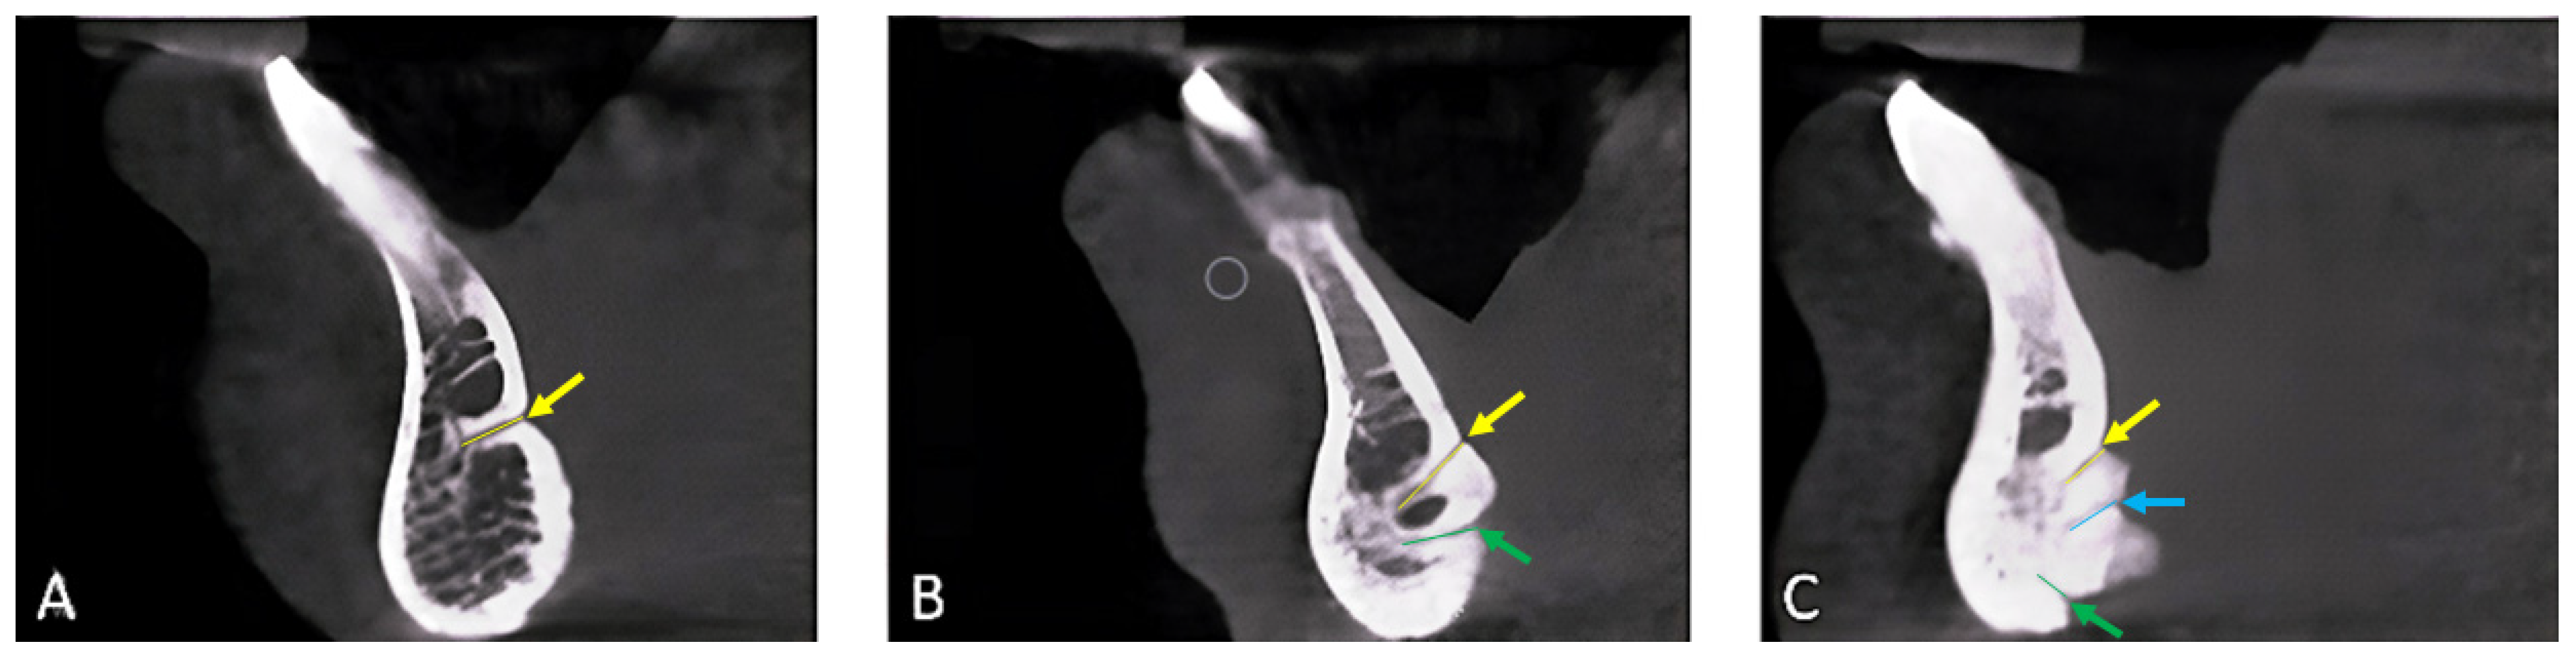

2.2. Data Collection, Image Reconstruction, and Assessments